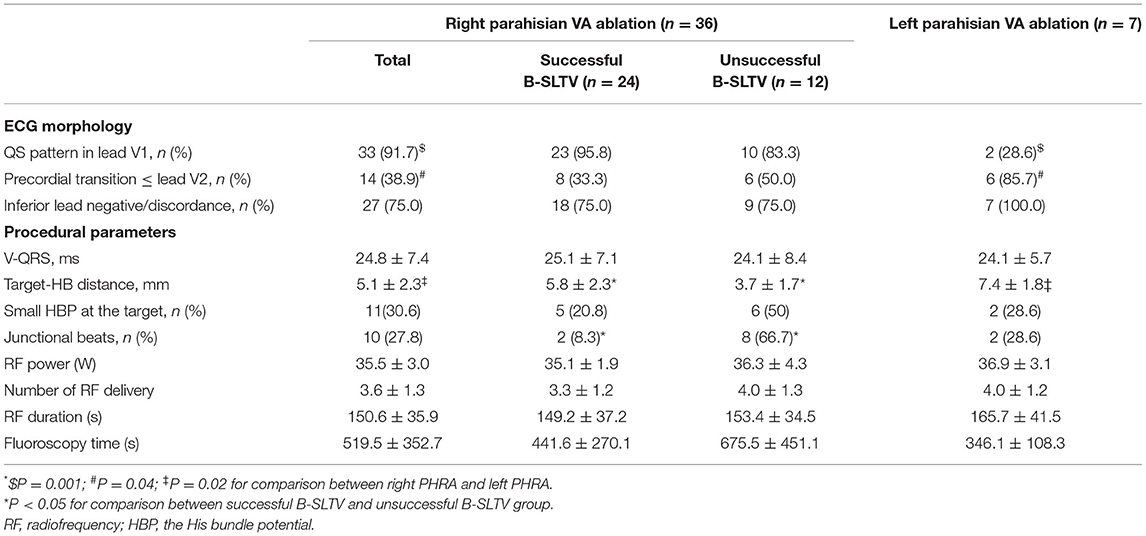

EP Mapping at the Preferential Regions

For right PHVAs, the B-SLTV region was preferentially mapped. To access to the subvalvular area, the ablation catheter was introduced to the right ventricle via a Swartz sheath (SR0 type, St. Jude Medical, MN, USA), then curved reversely and clockwise rotated the catheter and pulled it back toward the tricuspid annulus, to form catheter inversion configuration (Figures 2A–C). The position of the catheter tip was judged by fluoroscopy and confirmed by intracardiac echocardiography (ICE) imaging (CARTO Sound, Biosense Webster, CA, USA) (Figures 2D,H). For left PHVAs, the mapping catheter was advanced in the left ventricle via trans-aortic retrograde approach to map the left parahisian region and the septal region of mitral annulus (Figure 3).

Figure 2. The Catheter placement in the B-SLTV and A-SLTV approach. (A) The schematic diagram illustrating the catheter tip was reversely curved beneath the SLTV (RAO view). (B,C) The fluoroscopic images showing the catheter was reversely curved beneath the SLTV through a long sheath (RAO and LAO view). (D,H) The ultrasonic images confirmed the catheter placement beneath the SLTV. (E) The schematic diagram showing the catheter tip was directly placed above the SLTV (RAO view). (F,G) The fluoroscopic images showing the catheter tip was placed directly above the SLTV (RAO and LAO view). HB, the His bundle; CS, coronary sinus; ABL, the ablation catheter; SLTV, the septal leaflet of the tricuspid valve; ALTV, the anterior leaflet of the tricuspid valve; RA, the right atrium; RV, the right ventricle; LV, left ventricle; RAO, right anterior oblique; LAO, left anterior oblique.

If the attempt of B-SLTV ablation failed or was withdrawn due to safety concerns, the A-SLTV region (Figures 2E–G), contralateral parahisian regions and the neighboring structures (i.e., the coronary cusps at the aortic root) were mapped to search for an earlier activation site than the initial one, or the adjacent site that was just opposite to the initial lesion. They were served as a better target for subsequent ablation, or as a suitable target for anatomical ablation.

Judgement of B-SLTV placement of the catheter tip was vital for the B-SLTV approach. Although the fluoroscopic catheter inversion configuration indicated correct placement, it was doubtful that the catheter tip was at the right place in some cases. At this time the B-SLTV positioning could be judged by the fluoroscopic sign of catheter “fixation” while pulling it back, and could be further confirmed by ICE imaging (shown in Figures 2D,H). Even if the catheter tip was placed at the B-SLTV area, a contact-force sensing catheter was preferable and sometimes clockwise rotation of the catheter was needed to ensure appropriate catheter tip-tissue contact.